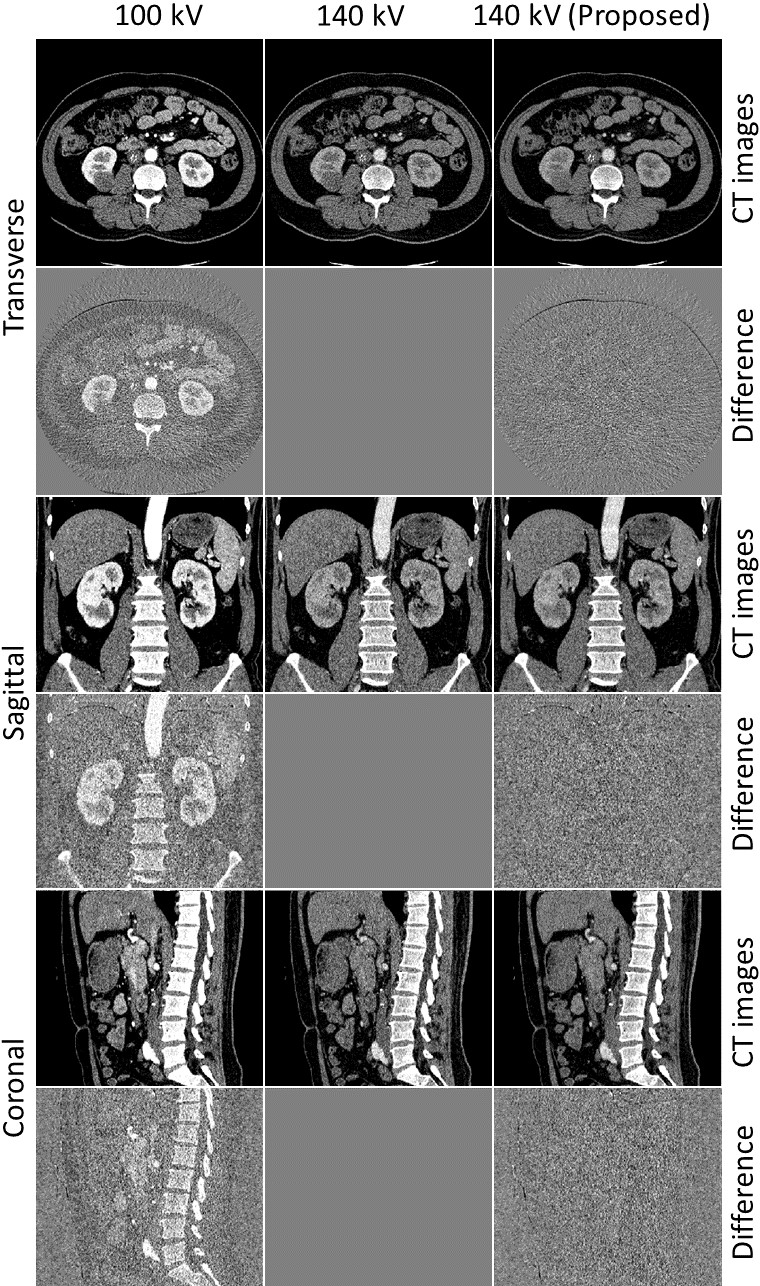

Figure 7: Example results on a testing slice and the difference with respect to the corresponding real high-energy image. The first, third and fifth row display the images on axial, sagittal and coronal view. From left to right are real 100 kV image, real 140 kV image and result from proposed method, respectively. The second, fourth and sixth row are the corresponding differences with real 140 kV images. The CT images are displayed with a window width=300 HU and center=50 HU while the difference images are displayed under window width=300 HU and center=0 HU.

We first focus on the results of equiangular geometry, and comparison results using different geometries are presented at the end this section. Fig. 7 shows original DECT images and the 140 kV images predicted using the proposed method for a testing patient. The first, second and third columns show the original 100 kV images, the original 140 kV images, and the predicted results, respectively. The first, third, and fifth rows show CT images in transverse, sagittal, and coronal planes, respectively. The second, fourth, and sixth rows show difference images with respect to the corresponding real high-energy CT images in transverse, sagittal, and coronal planes, respectively.

As can be seen, the proposed DL-derived high-energy images are highly consistent with the original high-energy images. There are some differences at sharp boundaries which also appear in difference images between original high- and low-images. Those differences may be motion introduced difference between original DECT images because there is approximately 90 degrees out of phase for the low- and high-energy data acquired using a dual-source DECT scanner. When inputting the low-energy image into the model, the model performed prediction based on the anatomical structure of the low image and can not reflect the change with respect to the original high-energy image.